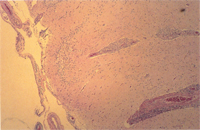

肉眼病變: 局部性慢性炎症見於整個腦組織,主要侵犯血管周圍形成很厚的非化膿性炎症細胞增生(圖1),包括淋巴球、組織球、類上皮細胞、吞噬細胞與少許漿細胞,偶爾亦有嗜中性球(圖2)。炎症細胞圍繞血管厚薄不一,圍繞不均勻,有時較集中於血管一端而呈偏心。又各種炎症細胞出現增生程度不均,有的圍繞為清一色淋巴球(圖3),有的則大部分為組織球或吞噬細胞(圖4)。特殊染色如PAS並無特殊發現,本病例又可看到一些血管變性(degenerated vessels)。病變發生於腦脊髓與腦膜,灰白質均可被侵犯,炎症細胞增生,侵犯非只限於血管周圍,亦可侵入腦實質neuropil。